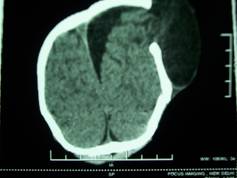

An 18 months old child was brought in with the history of fall 6 months back. He presented to us with the complaint of progressively enlarging swelling over left parietal region after the trauma. There was no history of any vomiting, seizures or any discharge from ear or nose. The patient was conscious and crying, with no focal neurological deficit. He had soft, cystic non-tender left parietal scalp swelling with visible brain pulsations. X-Ray skull showed wide left parietal bone defect. NCCT scan brain along with 3D reconstruction was done, which showed large left parietal skull defect measuring about 10cm x 4cm (Figure-1). There was a large CSF collection associated with herniation of brain matter through the skull defect, below the scalp, leading to a large cystic scalp swelling. There was an associated large left parafalcine CSF collection (Figure-2 and Figure-3).

Figure 3: Herniation of brain matter through the skull defect, below the scalp, leading to a large cystic scalp swelling with associated large left parafalcine CSF collection in axial section.

<b>Figure 3: Herniation of brain matter through the skull defect, below the scalp, leading to a large cystic scalp swelling with associated large left parafalcine CSF collection in axial section. </b>